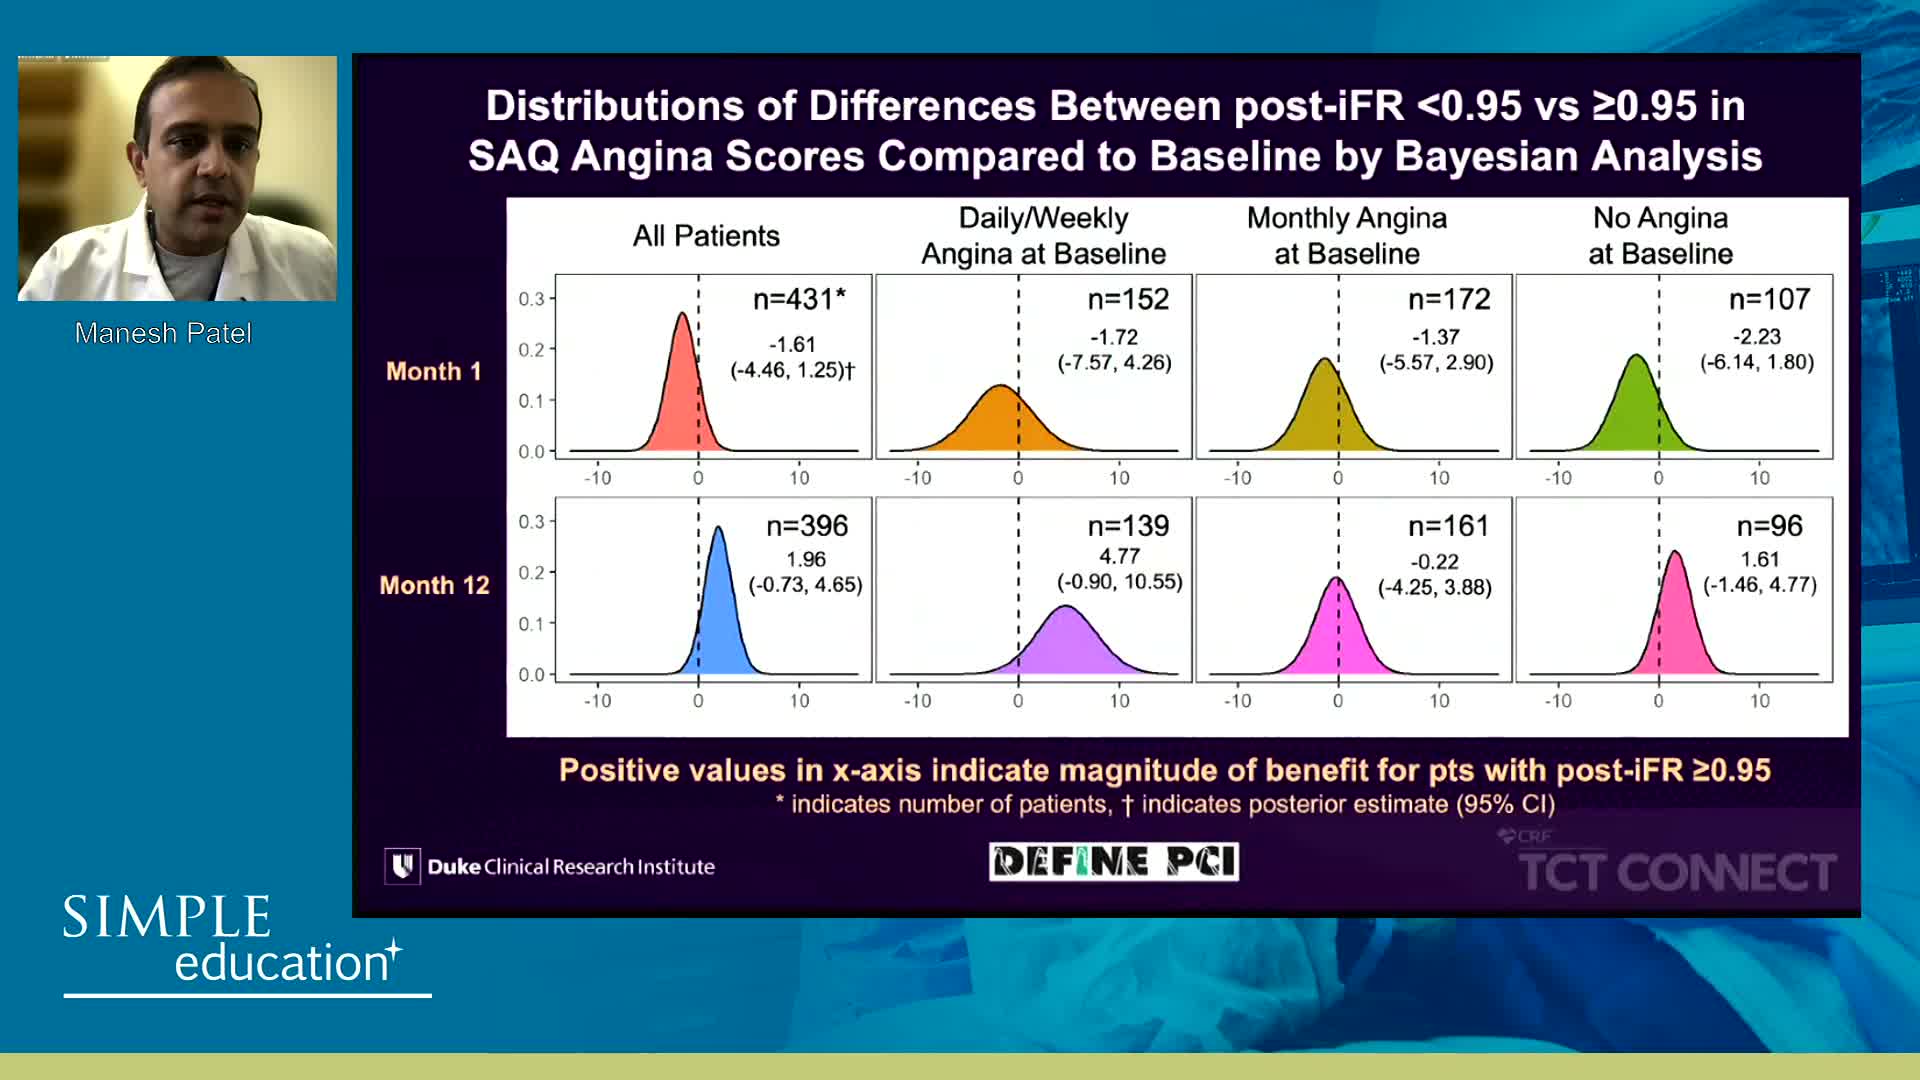

DEFINE-GPS Leading to Full Integration of Coronary Physiology to PCI Decision-Making

DEFINE-GPS leading to full integration of coronary physiology to PCI decision-making

Coronary physiology gate keeper or guide to coronary PCI? Rationale and design of DEFINE-GPS

iFR or FFR in the LAD. What does the clinical outcome data tell us? - Dr Sayan Sen

Breakout session: Common pitfalls of FFR and iFR assessment - Dr Ricardo Petraco